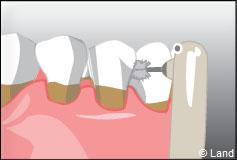

LES BROSSETTES INTER DENTAIRES :

Les brossettes inter dentaires sont indispensables si les espaces entre les dents sont élargis ou s’il y a une maladie parodontale. Leur taille sera adaptée pour chaque patient sur prescription du chirurgien-dentiste.